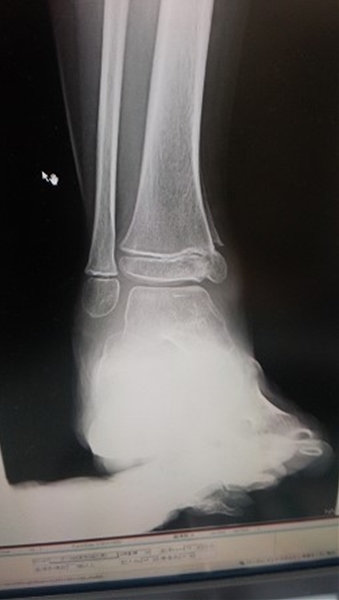

2日にギプスの取れた次男

見た目は大変元気

骨もしっかり出来てきてる(らしい)

良く見てもわからんw

9割がた治ってるはずなんだけど・・・

まだ片足引きずって歩いてます